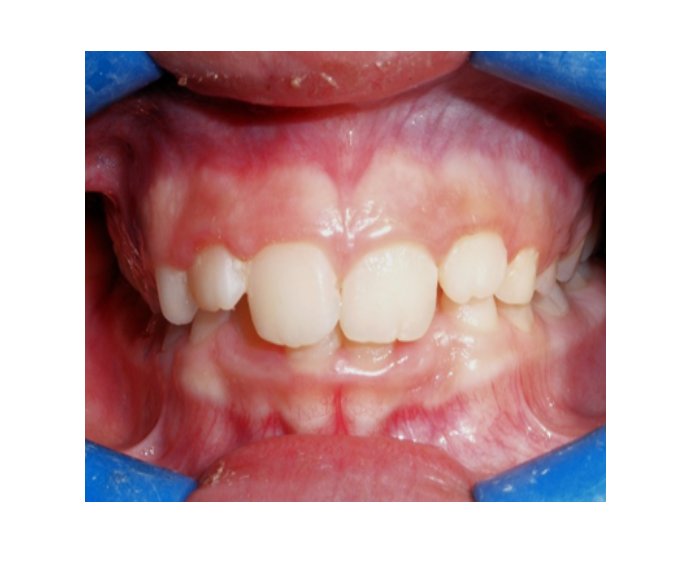

Mordida Cruzada anterior unidental